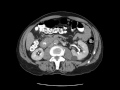

Duodenal adenocarcinoma

MRI and CT images nicely demonstrate mass-like thickening of the decending duodendum. Notice the prominent restricted diffusion associated this thickening. This was found to be duodenal adenocarcinoma at biopsy